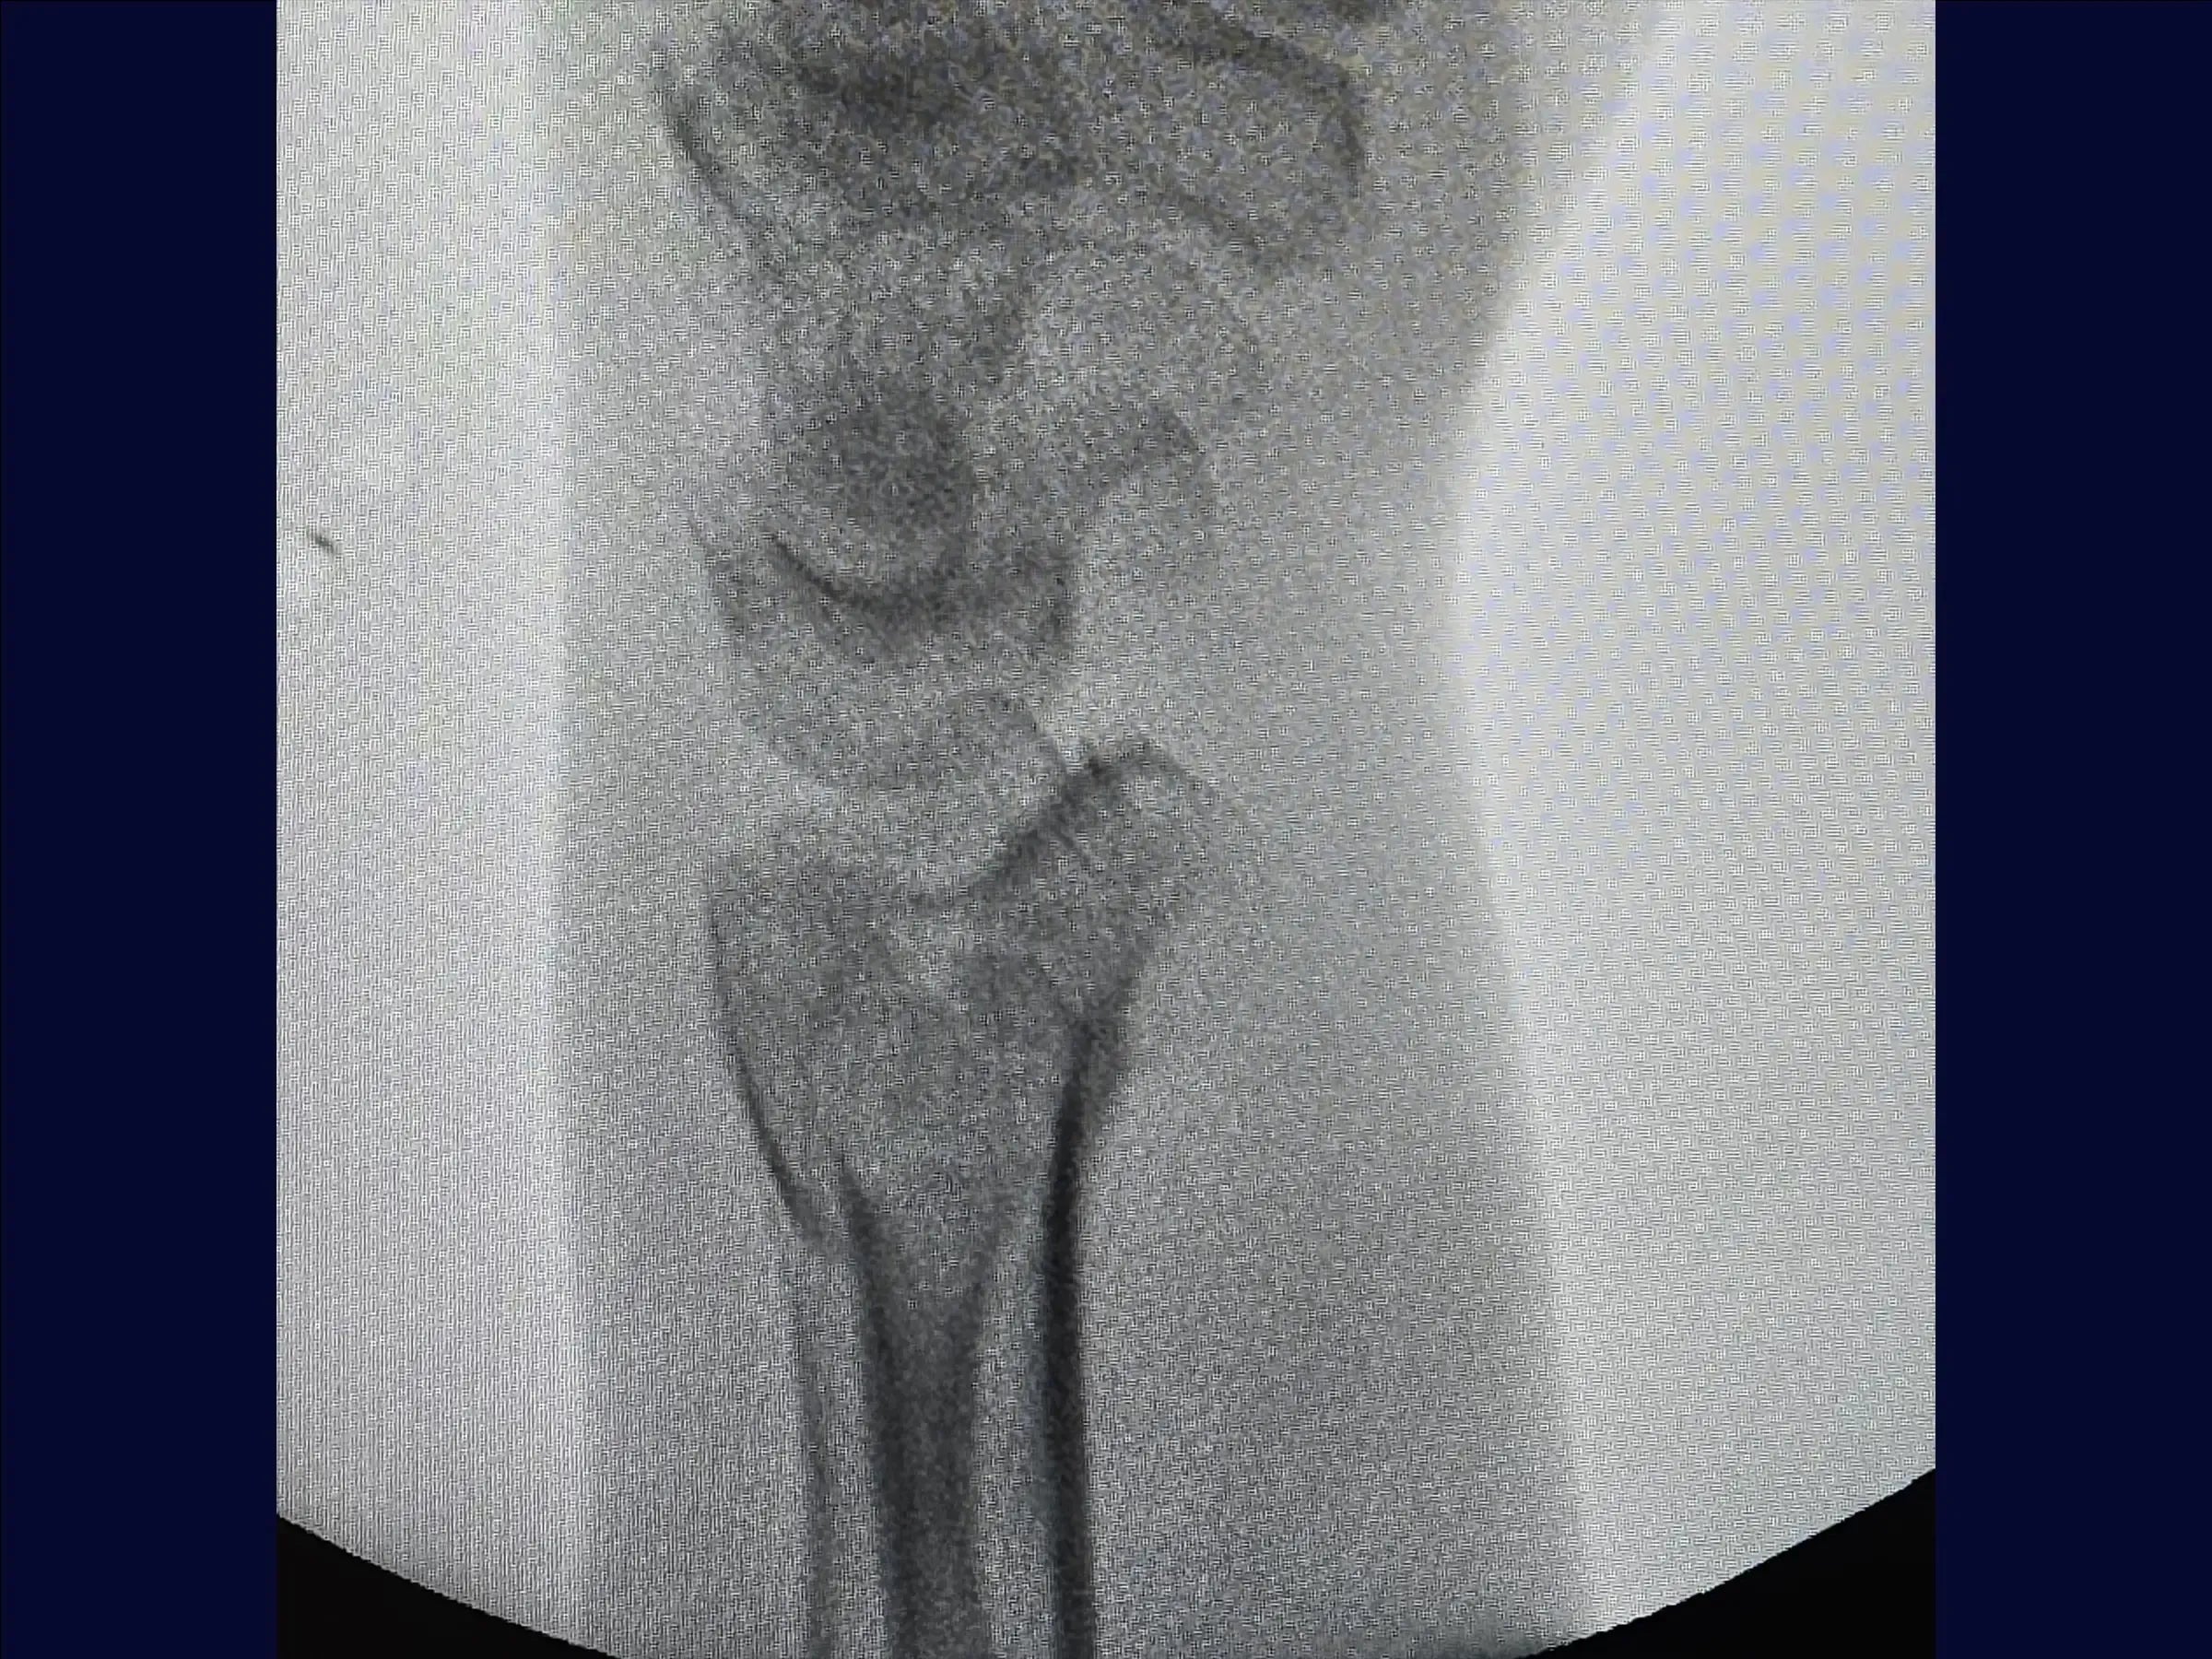

- Evaluación y reducción provisional: La formación abarca el análisis de imágenes de fracturas multifragmentarias del radio distal y la reducción por tracción manual ( ligamentotaxis ). Incluye la fijación percutánea provisional con alambres a la estiloides radial y al tubérculo de Lister para estabilizar los fragmentos.